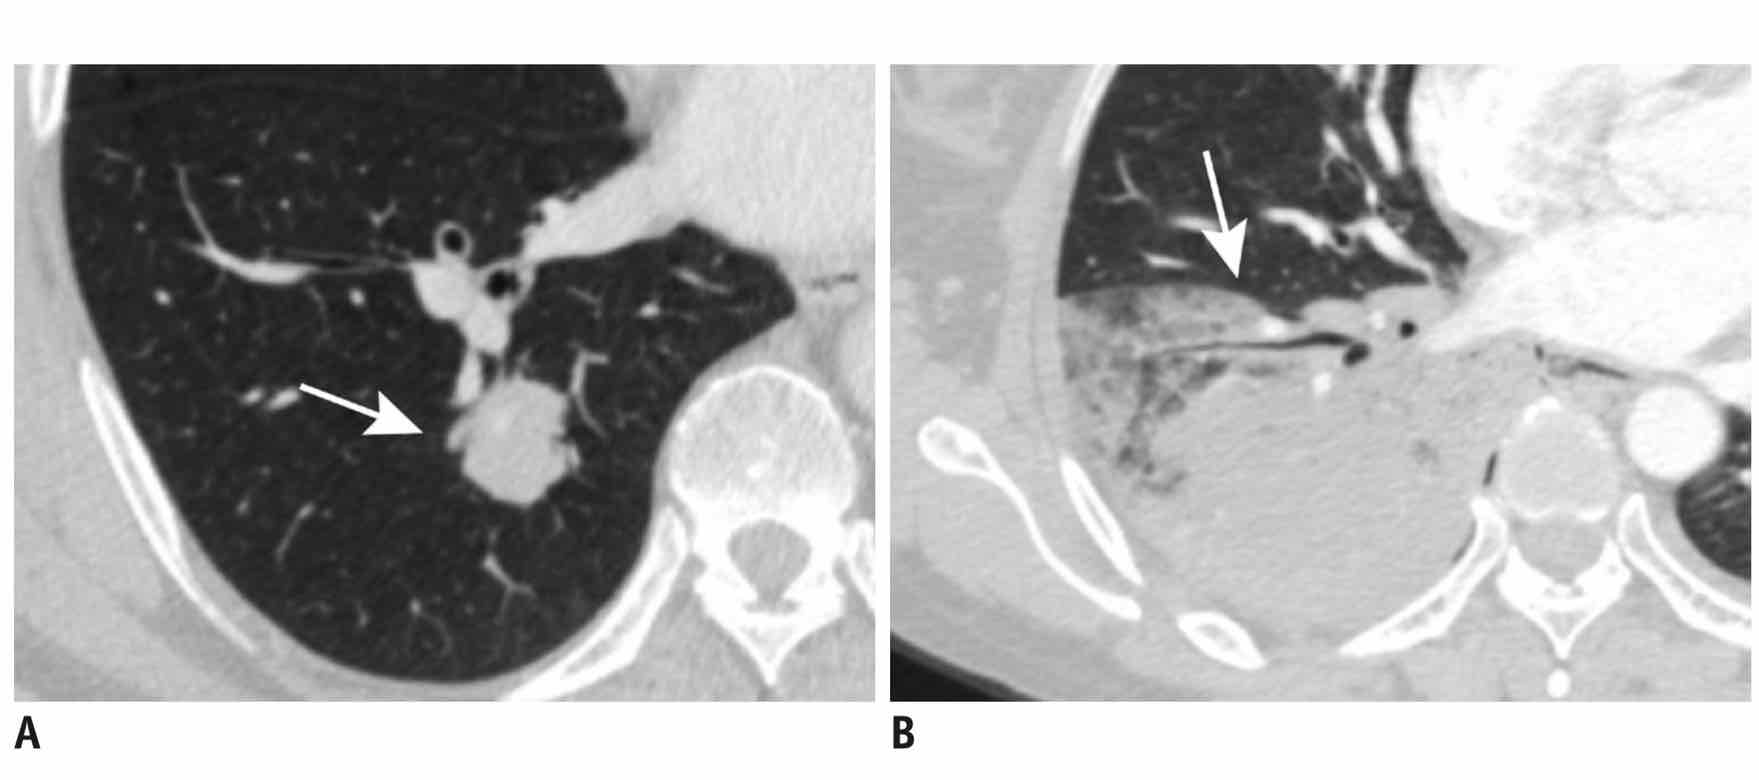

左图为孤立型 IMA,右图为肺炎型 IMA。

虽然我们不具备专业医生的读片能力,但这里其实相对容易的能看出两图之间的区别:

1. 孤立型的肺粘液腺癌主灶普遍呈现为一个有固定形状的独立物质;

2. 肺炎型的肺黏液腺癌主灶普遍呈现为一团在肺叶中广泛分布的肿瘤;